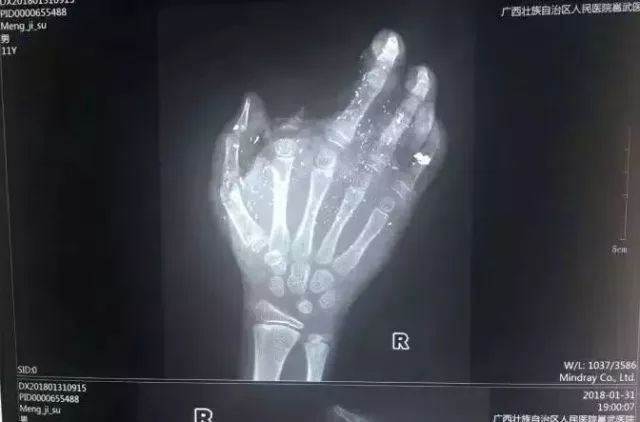

手机爆炸致男孩手掌被炸伤 2018年1月31日,广西发生一起手机爆炸事件,一名年仅12岁的小男孩手掌被炸得血肉模糊,右手食指被炸没了,拇指、中指、无名指也都炸伤,失去了供血,手掌皮肤被炸得稀烂。

经CT检查,右眼内有2块手机碎片。据了解,手机之前出现过充电时发热现象,但家长当时未在意。